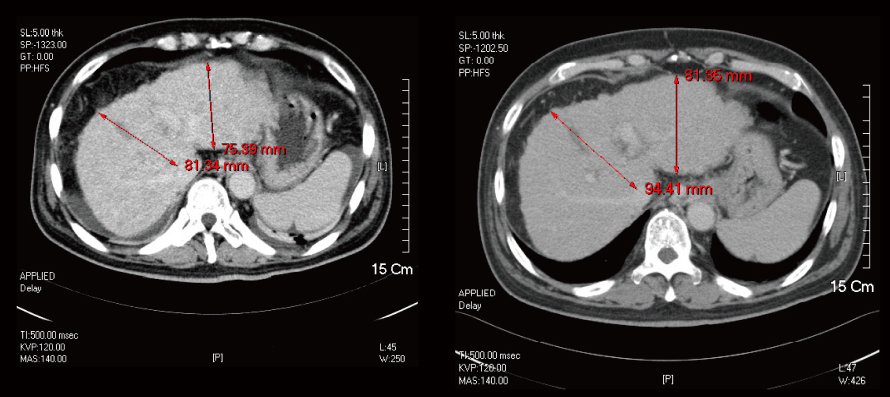

간경화

Liver Cirrhosis

간의 크기가 598.98ml에서 915.36ml로 회복되었습니다.